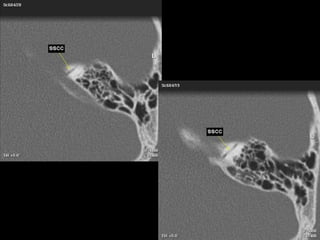

IAC MRI Anatomy and Search Pattern :

3D CISS sequence (thin axial high T2 sequences)

Finally:

Evaluate the following fluid filled

structures that are T2 bright:

•Semicircular canals

•Vestibule

•Ovoid in shape

•Cochlea

•Modiolus: hypointense area

at base